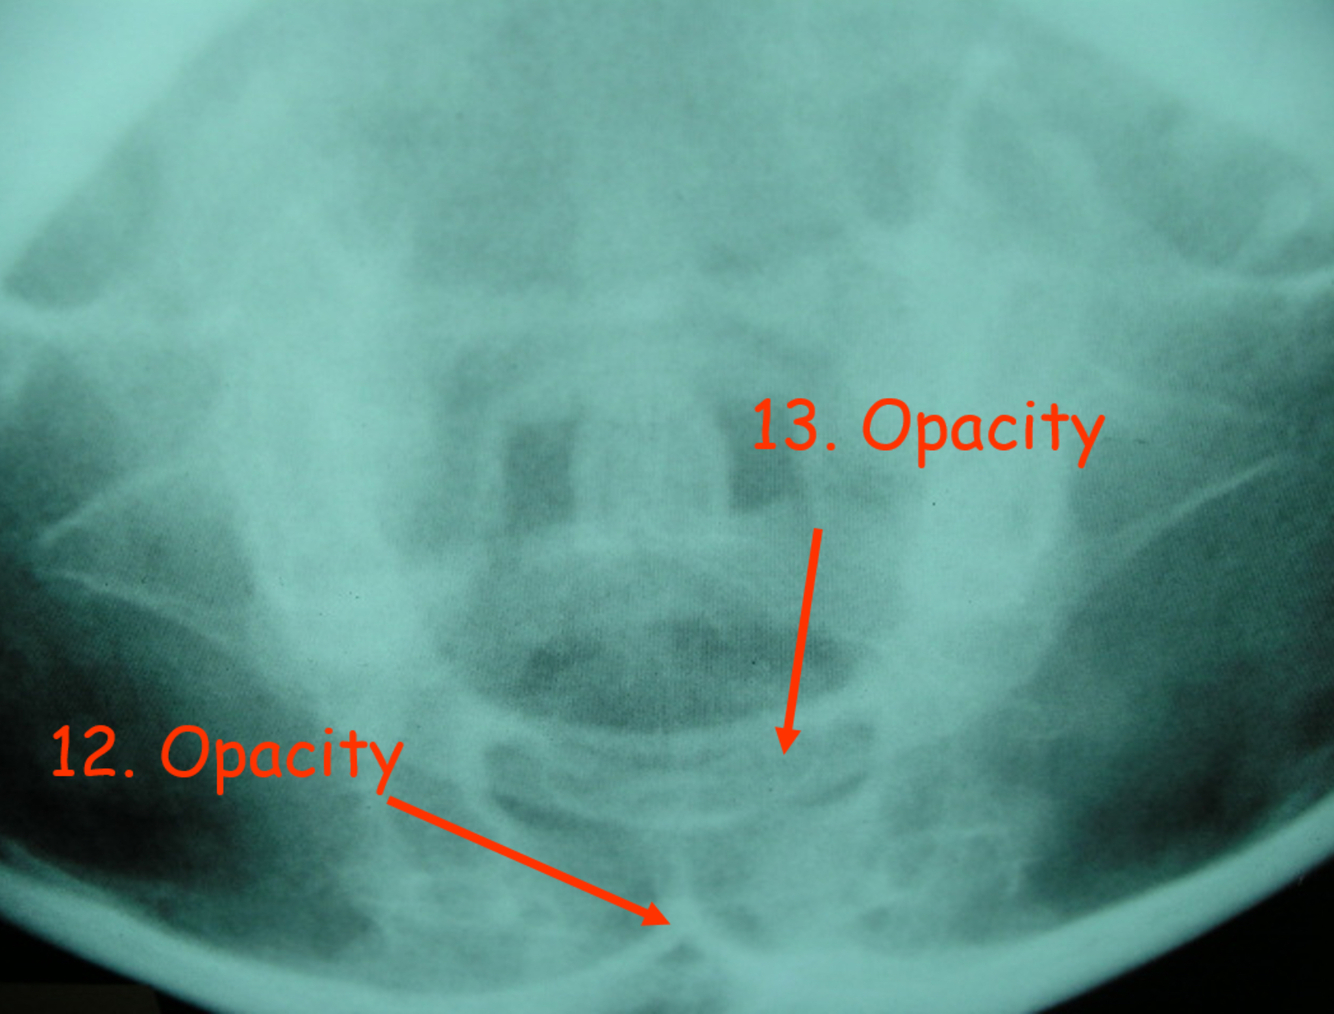

What is 12?

pars interarticularis